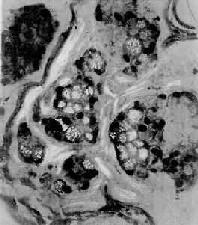

图10-19 粘液

细胞成团,胞浆内充满大量粘液,核被挤向一侧,呈印戒状